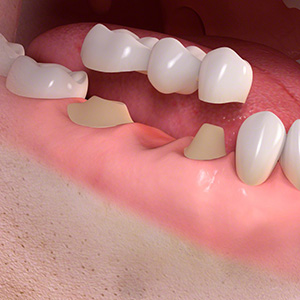

ブリッジ

次にブリッジですが、構造は歯を失った部分の前後の歯を全て削り3つ連なった被せ物を入れる治療法です。

| メリット | デメリット |

| 元あった歯と同じサイズなので異物感が少ないという点と自分の歯の様な感覚で噛むことができるという点です。 |

前後の健康な歯を削らなければならない。 ※ただし噛み合わせや歯の状態・部位などを考慮すれば支えの歯の寿命が短くなることはありません。 |